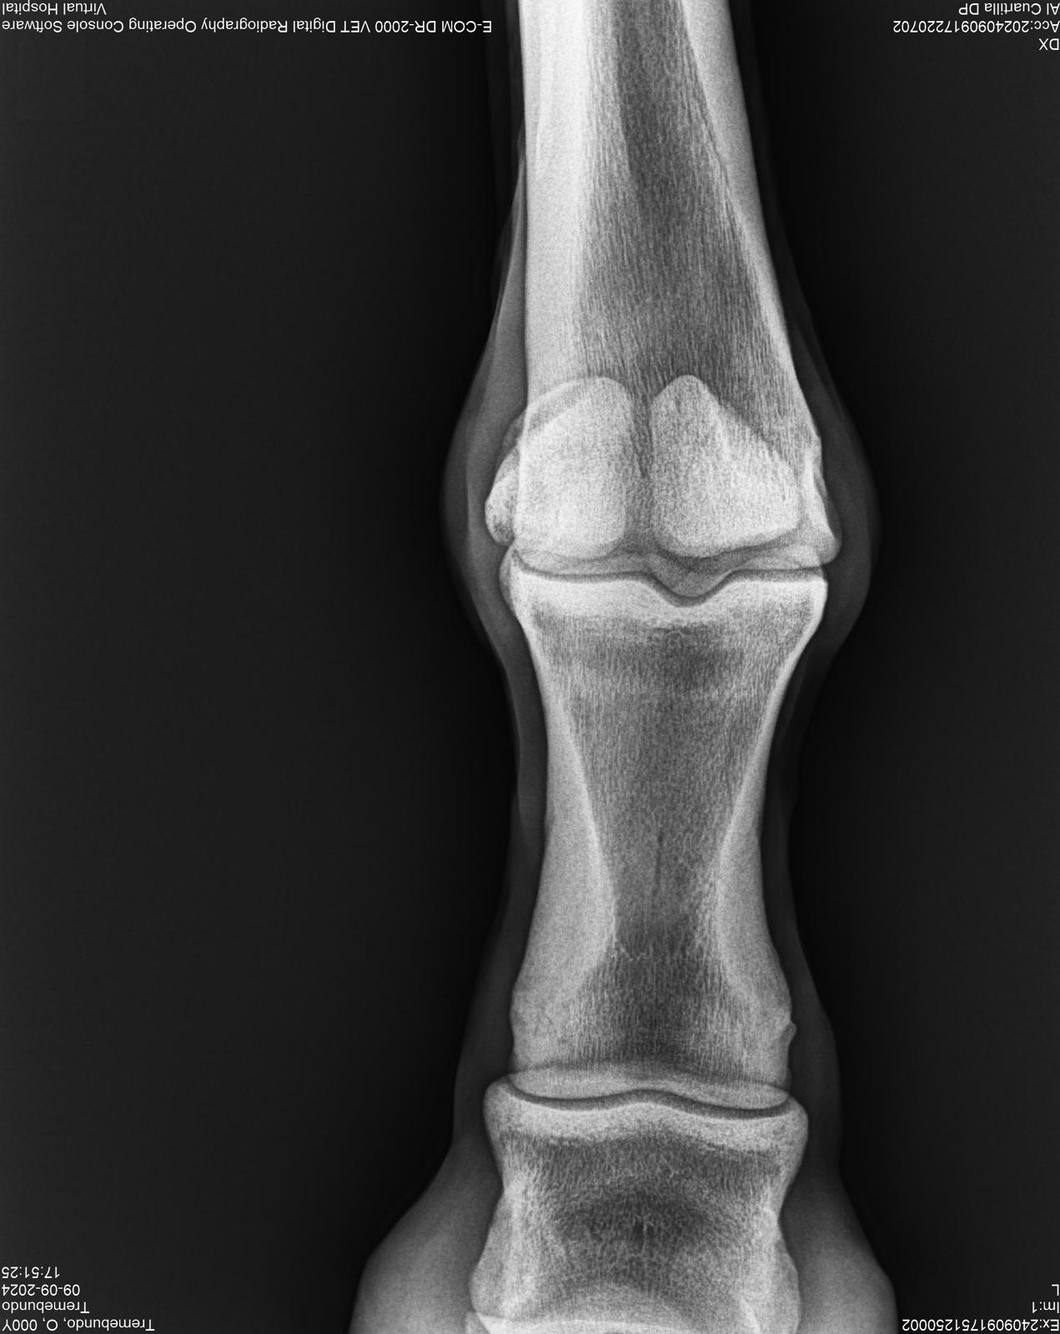

LOTE 37, TREMEBUNDO

Ficha del Lote

Identificador: #291140-

Generacion 2022